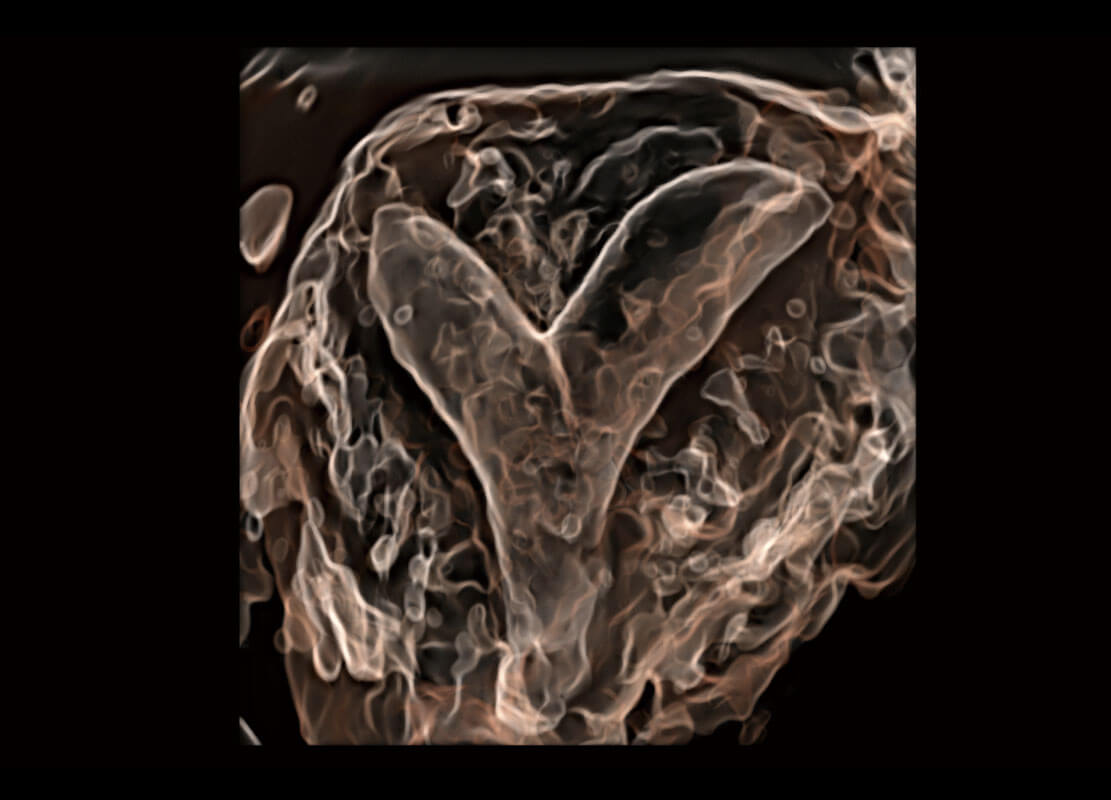

腔内三维-光影成像

光影成像-孕囊

胎心容积成像